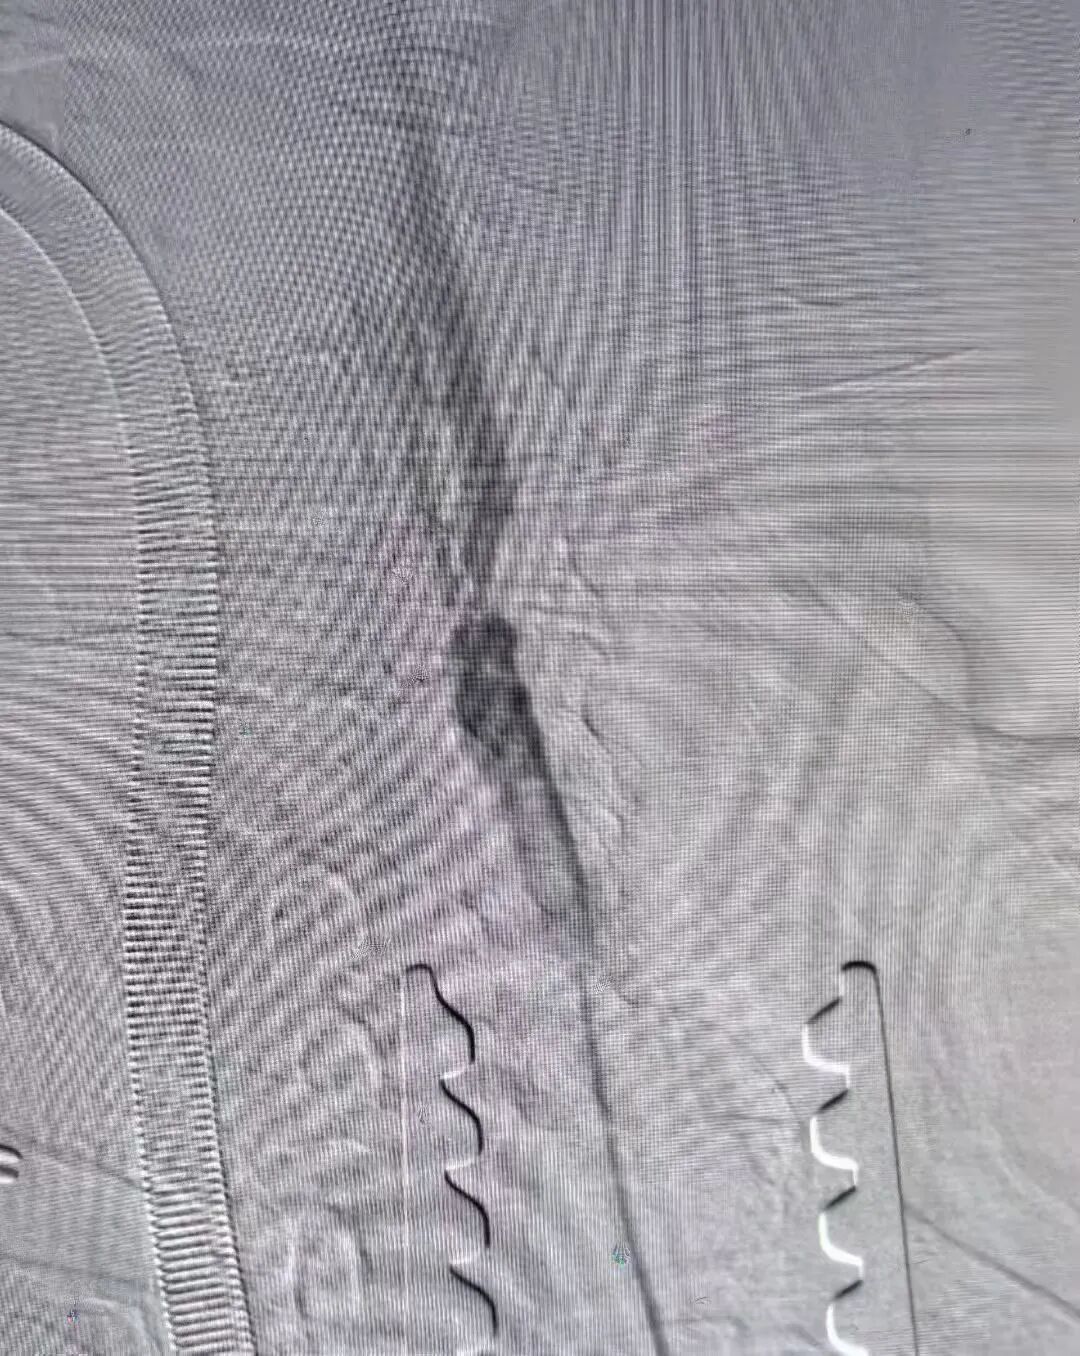

术前及术后造影图像:

本次手术由我院心脏血管外科核心团队主导,术前联合麻醉科、影像科等多学科进行全面评估,制定个性化手术方案;由兴安盟人民医院特聘教授刘鹏、兴安盟人民医院副院长周智勇主刀,术中团队密切配合,精准操作每一步,历时1.5小时顺利完成,术后患者生命体征平稳,无并发症发生,目前已顺利康复。